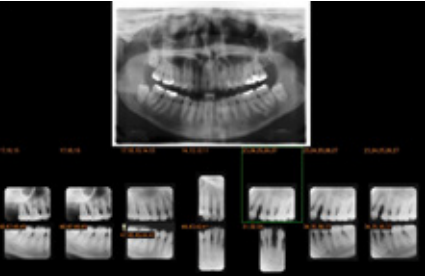

牙科影像系统:提供前端排片数字符化流程工具,简化牙位输入流程。并可依需求自定挂片模式,包含全口、Bitewing、根尖、儿童等。